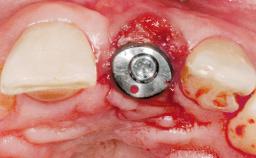

Immediate Flapless Placement of an Implant in a Maxillary Left Central Incisor Site

A 29-year-old female patient presented for treatment to replace the upper left central incisor tooth with an implant- supported restoration. The tooth had been intermittently symptomatic for the previous 12 months. The tooth had originally suffered trauma about 15 years previously. Several endodontic treatments had been performed, including an apicectomy procedure to retain the tooth. The patient was healthy and a non-smoker. She had reasonable expectations in regard to esthetic outcomes and the risk of marginal tissue recession following treatment. At medium smile, the gingival margins of the upper teeth were visible, with a display of 3 to 4 mm of the gingival margins. Gingival recession of tooth 21 and a discrepancy in the gingival levels between teeth 11 and 21 was observable during normal speech and smile.

Type of Implants One-Piece

Placement Protocol Immediate implant placement

Tooth Site Maxillary incisor or canine

Socket Morphology Single-root socket